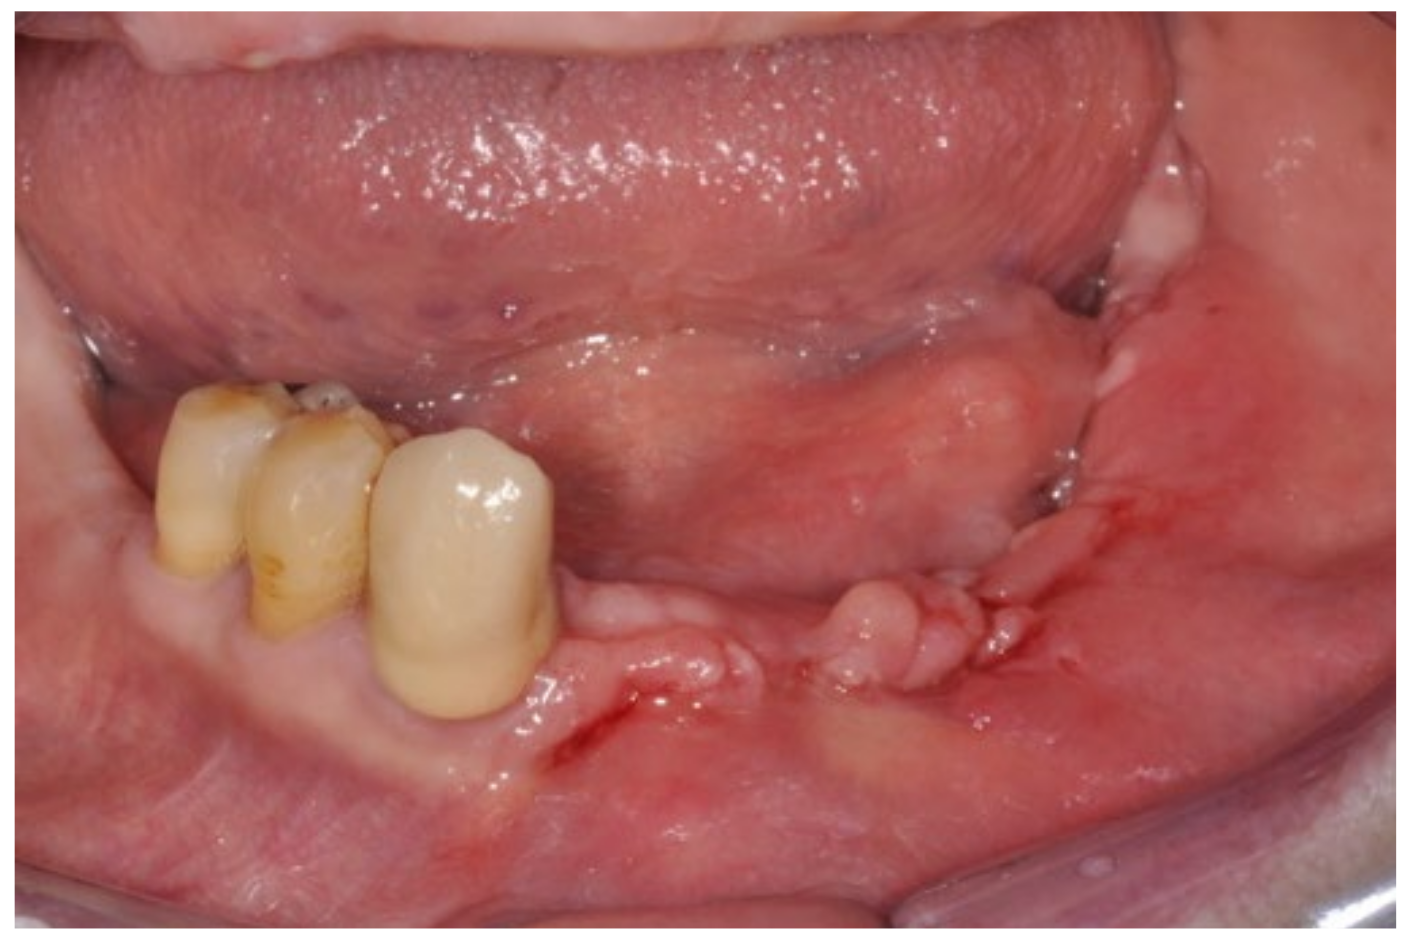

3.1. Clinical Case 1

3.2. Clinical Case 2

3.3. Clinical Case 3

3.4. Clinical Case 4

3.5. Clinical Case 5

3.6. Clinical Case 6